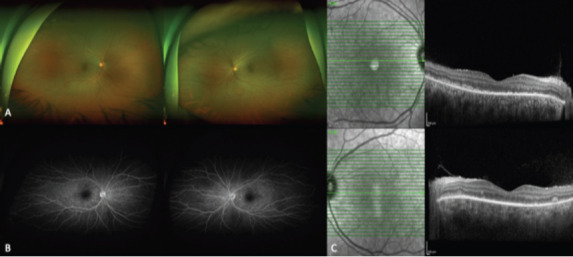

Case: We describe a case of a 32-year-old healthy lady who was admitted to neurology with the initial impression of aseptic meningitis. She had subacute onset of headache and fever, associated with blurring of vision and painful eye movements. Visual acuity 20/250 of the right eye and 20/80 of the left eye. Intra-ocular pressure measured 12 for the right eye and 14 for the left eye, and extraocular muscle movements were full Slit lamp examination showed a quite conjunctiva and clear cornea; however, there was an anterior chamber reaction of 2+ cells. The fundus exam showed mild vitritis with hyperemic disc swelling of both eyes and exudative retinal detachment bilaterally. Macular optical coherence tomography (OCT) demonstrated the presence of vitritis, pockets of subretinal fluids with bacillary layer detachment, and choroidal thickening. She was treated with steroids and mycophenolate mofetil with an excellent outcome.